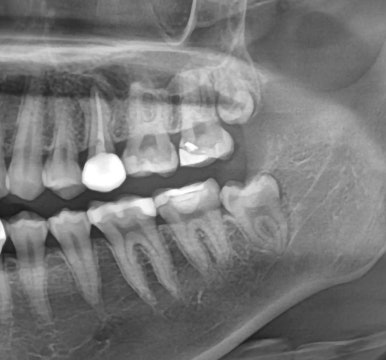

3. 사랑니에 충치가 생긴 경우

| 발치 전 구강사진 | 발치 전 엑스레이 | 발치 후 엑스레이 |

사랑니 위치는 수복 치료가 어렵고,

옆 치아까지 영향을 줄 수 있어 조기 발치를 권합니다.